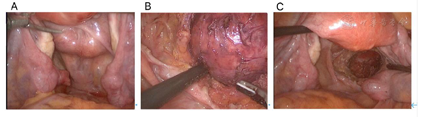

患者于2020年9月9日在全麻下行腹腔镜探查术(图4),术中见:腹膜后直肠右侧与右侧骶韧带之间可见一直径约6 cm的囊实性包块,稍向腹膜侧突起,包块与盆底周围组织广泛粘连,使包块固定于右侧盆腔深部,包块周围血供极其丰富,基底部较宽,位于骶尾骨右侧。向家属交代术中所见,家属要求行盆腔包块切除术,同时行双侧附件切除术。手术行腹腔镜下盆腔肿物切除术+双侧附件切除术,术中快速切片检查报告:(后腹膜盆腔肿瘤)良性病变,有无恶变待常规。剖视标本:后腹膜肿瘤增大直径约6 cm,囊实性,表面光滑。内为脂肪样物,囊壁光滑。术后标本给予家属过目后送病检。术后给予抗感染、抗凝及支持治疗。

病理检查结果见图5。

患者术后给予抗感染、抗凝及支持治疗,术后第2天通气,术后第3天通便,复查血:血红蛋白浓度109 g/L,血常规、肝肾功能、电解质、D二聚体均未提示明显异常。术后病检回报:(后腹膜盆腔肿瘤)皮样囊肿。左侧附件+右侧附件:1.(双侧)慢性输卵管炎伴积水及胚胎残余性囊肿。2.(左侧)卵巢白体形成,局灶查见陈旧性出血,请结合临床排除子宫内膜异位囊肿可能;(右侧)卵巢白体形成。腹腔冲洗液:(腹腔冲洗液)镜下见间皮细胞,淋巴细胞,中性粒细胞,未见肿瘤细胞。术后第7天腹部伤口拆线,Ⅱ/甲级愈合,出院。术后3个月随访,患者一般情况好,无下腹痛及其他不适,大小便正常,无盆腔神经损伤症状,复查盆腔彩超未提示明显异常。